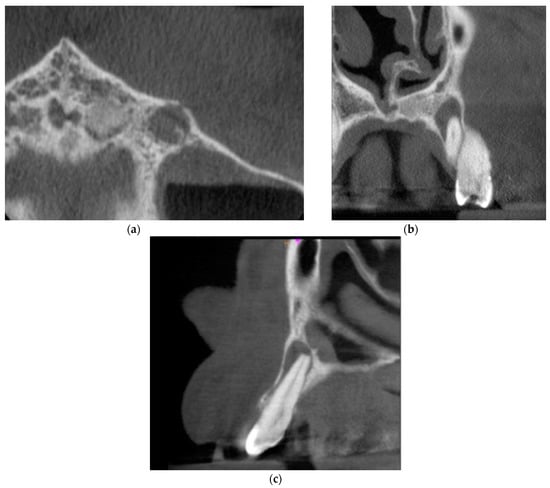

The third and final appointment was scheduled 6 months after the end of root canal treatment. Intraoral examination revealed healing progression. The gingiva was smooth, pink, and humid, with no pain on palpation. The mobility of the tooth was within the physiological limits (Grade 1 Miller mobility index). The reaction of tooth 23 to vertical and horizontal percussion was negative. PD max = 4 mm. The CBCT images presented healing of the periapical lesion. There was a small area of radiolucency around tooth no. 23 with the dimensions of 2.6 × 1.0 × 0.6 mm. Figure 4 presents the CBCT images of the periapical lesion healing process 6 months after the end of endodontic treatment.

Figure 4. CBCT images presenting the healing process of the periapical lesion around the root of tooth no. 23 (date of CBCT examination: 8 December 2020): (a) axial view; (b) coronal view; and (c) sagittal view.